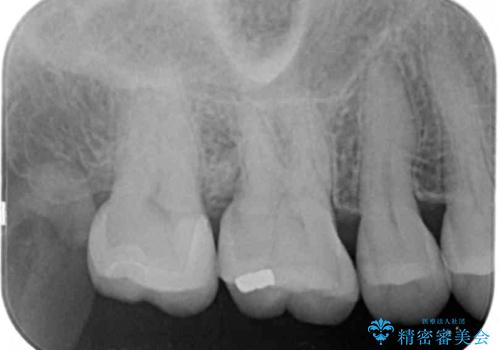

- 定期検診にて来院、症状はないものの右上の奥歯に虫歯が再発していました。

視診・レントゲン画像より虫歯の大きさを判断し、虫歯の除去後セラミックインレーにて修復することになりました。

- 右上7 セラミックインレー 77000円×1本費用は治療当時の料金となります